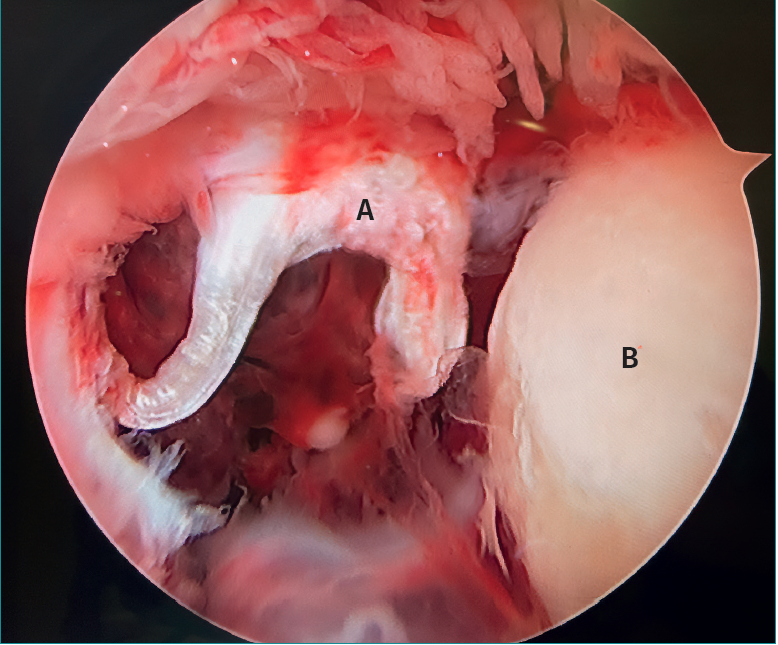

Anterior ankle arthroscopy in a patient with a Maisonneuve fracture (fracture of the posterior malleolus, fracture of the neck of the fibula, anterior tibiofibular ligament tear and syndesmosis).

The letter A shows the tear of the anteroinferior tibiofibular ligament or Bassett's ligament, which takes on a shape similar to that of the letter pi. The talus is identified by the letter B.